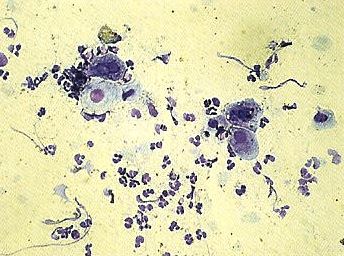

Scheidenabstrich VaginitisScheidenentzündungen sind eine häufige Ursache von Unfruchtbarkeit bei Zuchthündinnen und müssen deshalb sorgfältig diagnostiziert und behandelt werden. Die Diagnose ist aber meist sehr schwierig. Die Untersuchung des hinteren Abschnitts der Vagina mit Hilfe eines Spekulums oder die Beurteilung von Vaginalabstrichen können zwar hilfreich sein (häufig stellt man zahlreiche weisse Blutkörperchen fest), die Methode der Wahl ist jedoch die Vaginoskopie. Dabei wird ein kleines Endoskop in die Vagina eingeführt, um den genauen Zustand des Organs direkt visuell zu beurteilen. Lokale und systemische antibiotische Behandlungen müssen von längerer Dauer sein, da Antibiotika nur sehr schlecht in dieses Organ eindringen.

Durch einen Scheidenabstrich kann man Vaginitits diagnostizieren. Man bemerkt viele kleine Blutkörperchen.